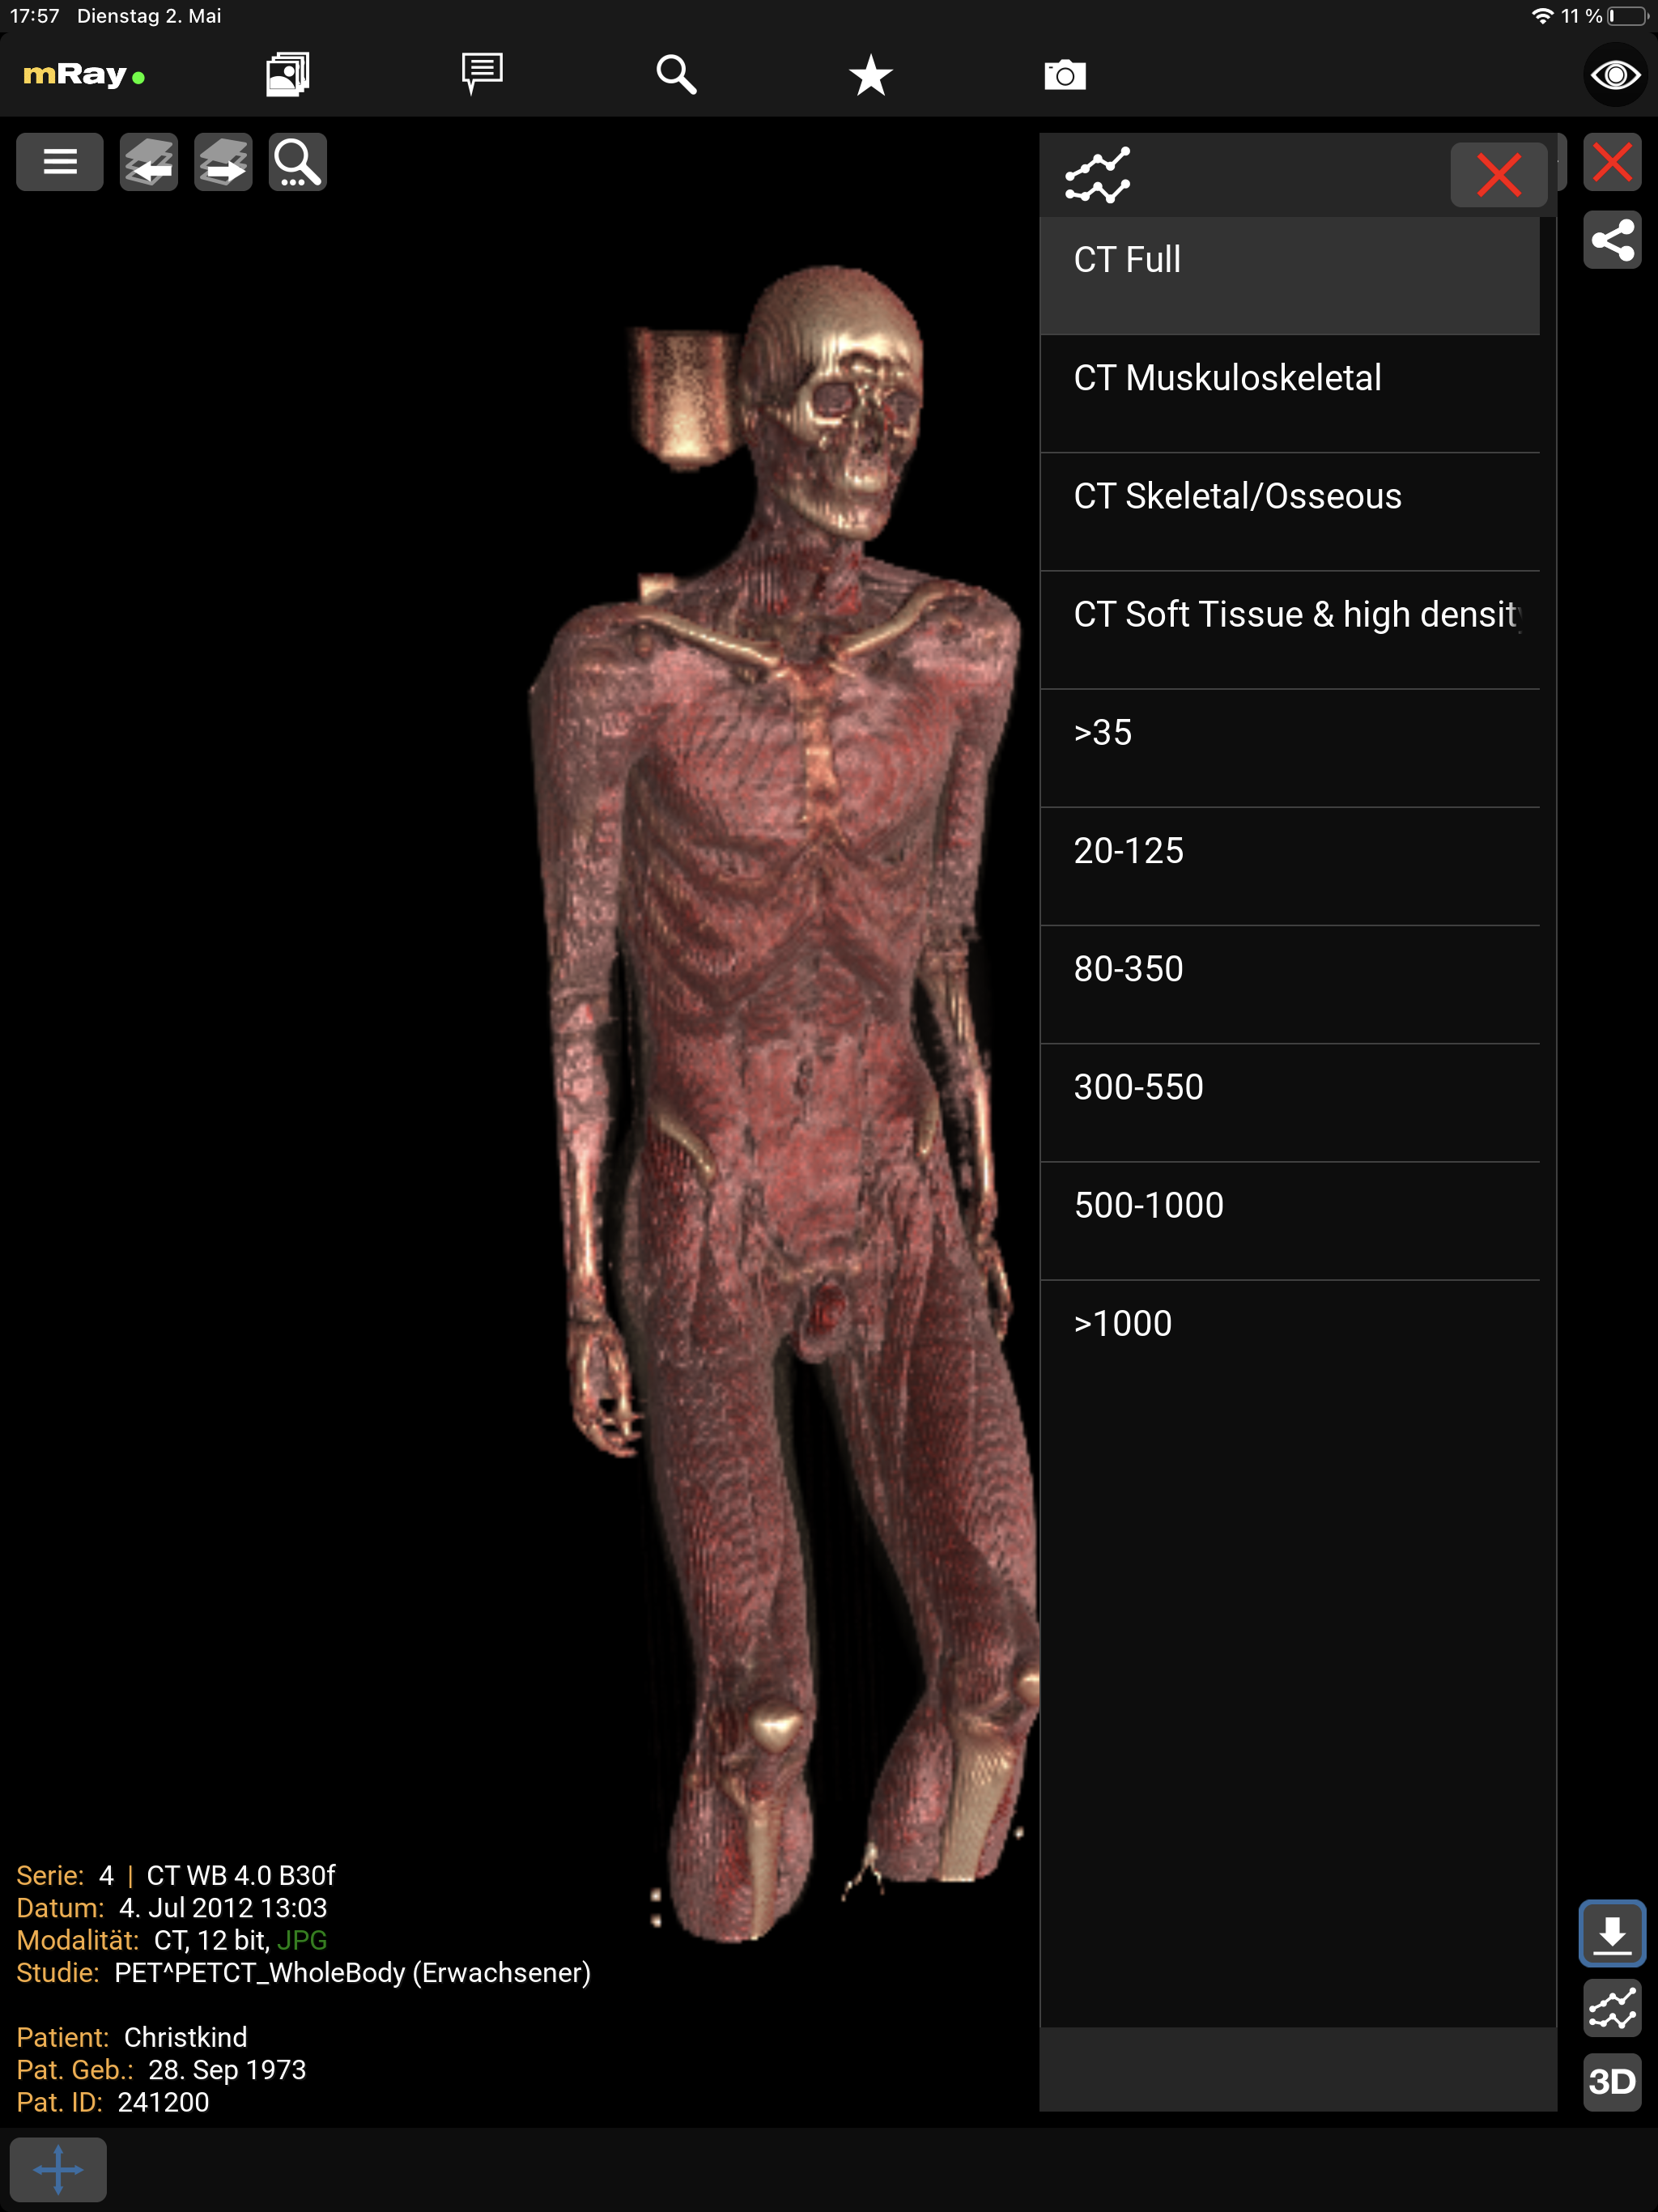

10.4.2. Volumen-Rendering

Das Volumen-Rendering erlaubt die Darstellung eines CT oder MRT Datensatzes in 3D. Aktivieren können Sie die Funktion im Werkzeugmenü, falls diese für den aktuellen Datensatz verfügbar ist. Um die Darstellung anzupassen, wählen Sie eine der voreingestellten Gewebe- bzw. Grauwertvisualisierungen aus. Die Ansicht können Sie mittels Touch bzw. linker Maustaste bewegen. Zum Zoomen verwenden Sie die Pinch-Geste bzw. die rechte Maustaste.

Der Screenshot zeigt die Auswahl der Grauwertvisualisierung.

|

Es handelt sich bei der Darstellung lediglich um eine Approximation. Diagnoseentscheidungen sollten sich auf der konventionellen Darstellung stützen. |

|

Setzt ein OpenGL-3.0 fähiges Gerät voraus. Die Volumen-Rendering-Funktion steht sonst nicht zur Verfügung. |